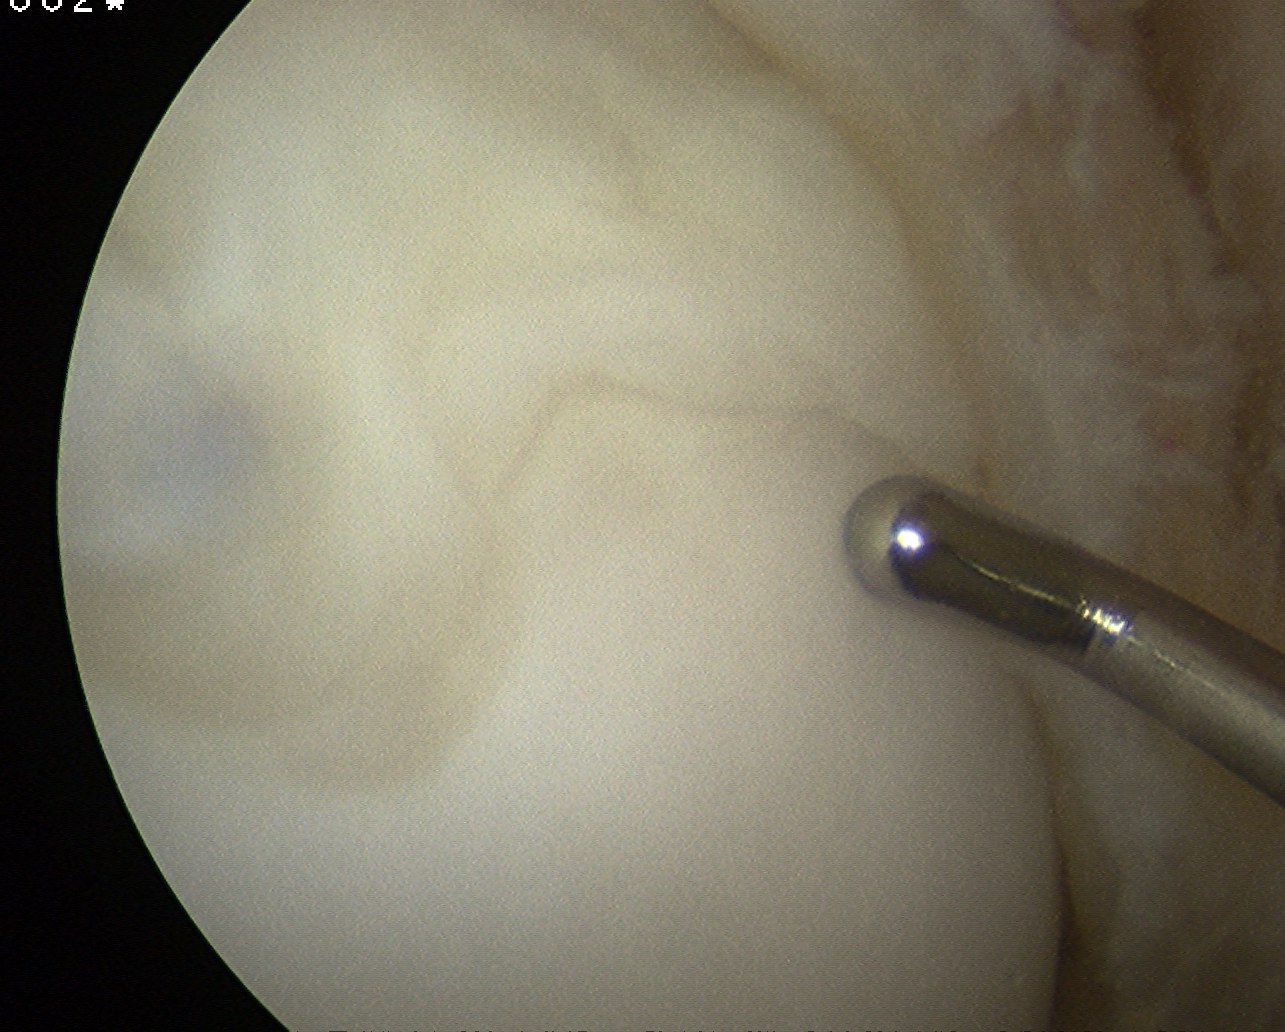

Arthroscopy

Arthroscope in lateral portal

- instrument through medial portal

- ensure can visualise entire fragment